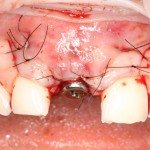

Через неделю можно снять швы. Область раны выглядит следующим образом:

А через два месяца — вот так:

На этом этапе, для создания более правильного десневого контура, можно поменять формирователь размер больше:

А еще через месяц — поставить временную коронку: